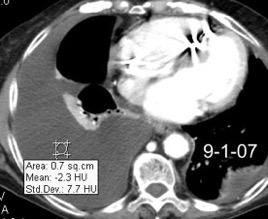

Hemorrágica………….30-70 UH

Extravasación iv. con sangrado activo……….>90 UH

“Simpático”………….,,,,<15 UH

Durso AM et al. Penetrating Thoracic Injury. Radiol Clin N Am 2015.

Urogénico……………….< 15 UH

Entérico.. ………………+/- 15UH

Biliar, Quiloso……………..<0 UH

Abramowitz1 Y et al. Pleural Effusion: Characterization with CT Attenuation Values and CT Appearance .AJR 2008